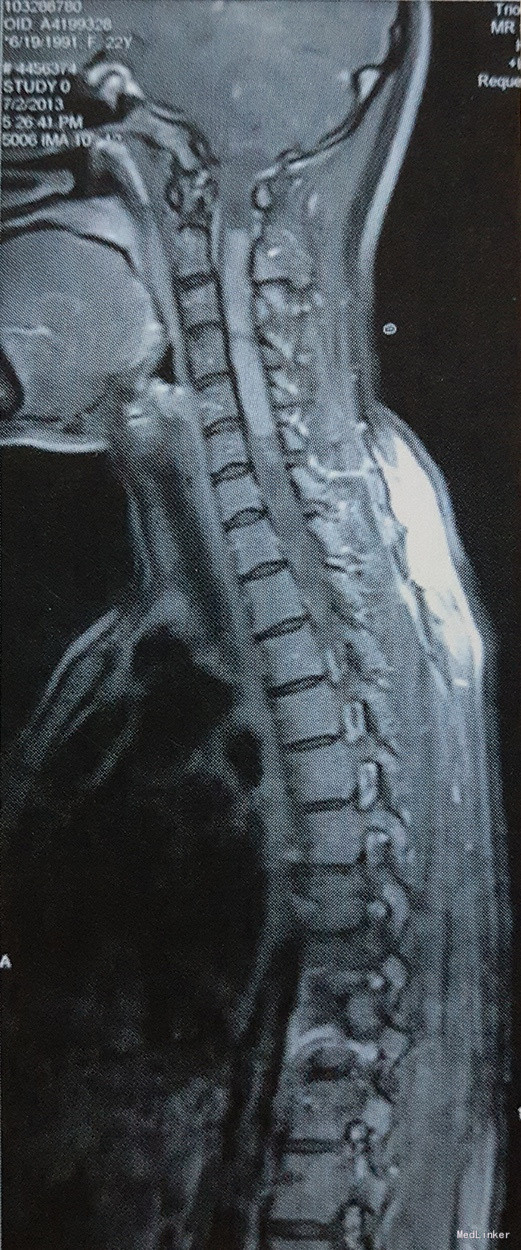

体格检查:左上肢肌力III级,右上肢及双下肢肌力IV级,肌张力降低。左上肢无法上举,右上肢运动正常。左上肢肘关节至肢端浅感觉消失,肘关节以上浅感觉减退;右上肢浅感觉减退,双下肢及躯干深浅感觉未见明显异常。心肺腹体检无明显异常。 影像学:全脊髓MRI结果:延髓-C5椎体平面颈髓稍增粗,可见等T1,等长T2信号,增强扫描均匀强化,下方脊髓可见囊性长T1,长T2信号,下方病灶延伸至T8平面,T9-L1平面脊髓T2信号增高,无明显强化。考虑:1、延髓-C5椎体平面髓内囊实行占位性病变,强化明显,考虑星形细胞瘤可能性大;2、其下方至T8椎体平面脊髓空洞形成。3、T8-L1椎体平面脊髓变性。